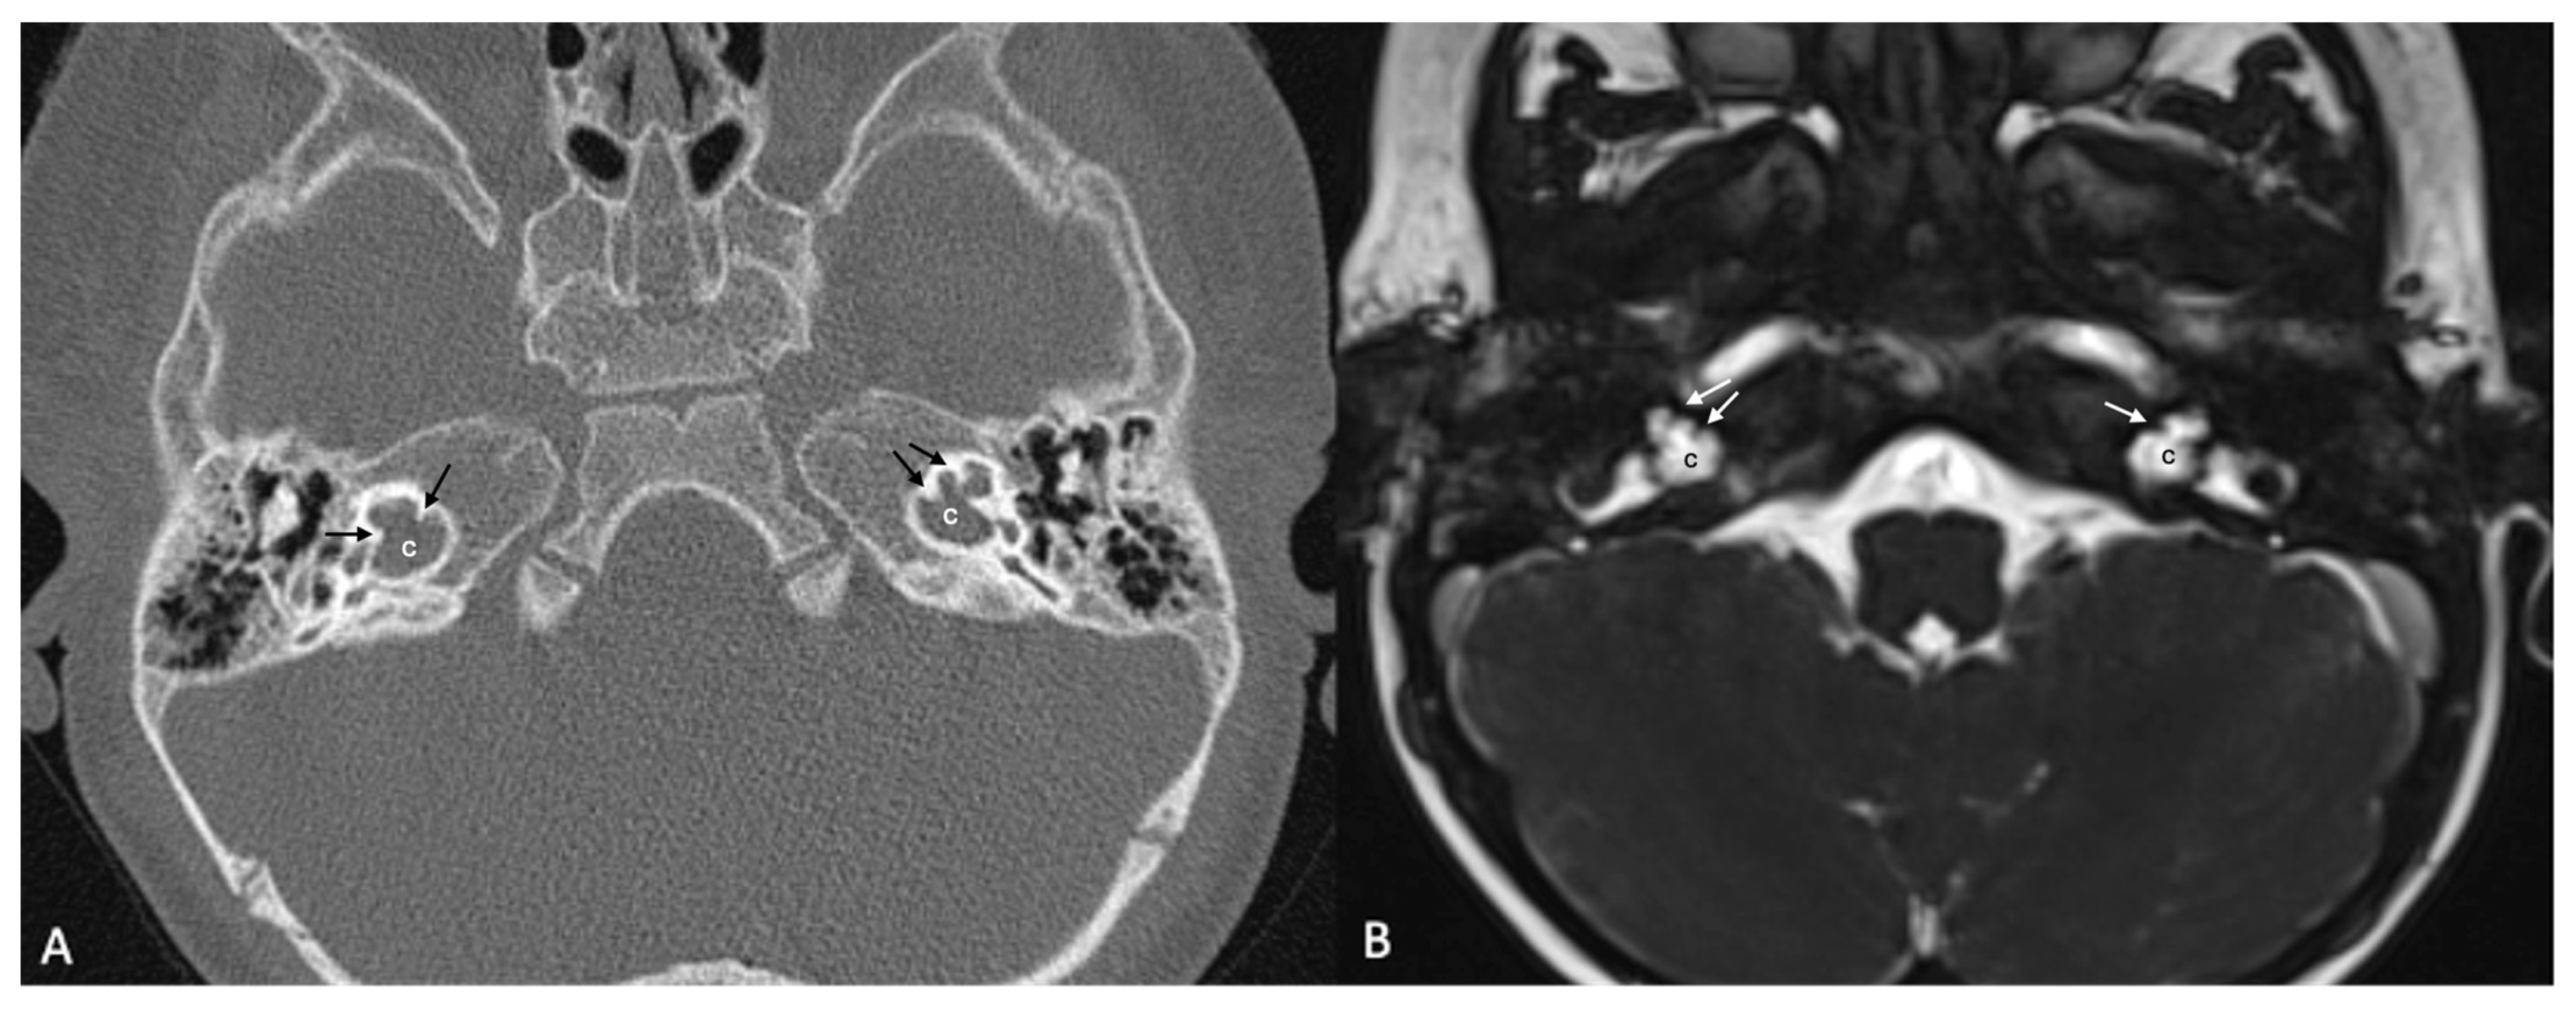

One patient exhibited IP-1 in the right ear and LA in the left ear. The right vestibule was hypoplastic, and the SCCs appeared as a single bud. The diameters of the right IAC and cochlear nerve were within normal limits. However, the stapes, oval and round windows, cochlea, vestibule, SCCs, IAC, and vestibulocochlear nerve could not be detected in the left ear. Cochlear implantation was performed in the right ear of this patient (Figure 3). Bilateral IP-3 anomalies were detected in two siblings. In these cases, the oval and round windows were also malformed. While both cochlear nerves of one sibling exhibited hypoplasia, the cochlear nerves of the other sibling were within normal limits as they were thicker than the facial nerves (Figure 4).

Figure 4.

(A) CT and (B) MRI images of a case of bilateral IP-3 (incomplete partition type-3). Note that despite the relative preservation of the outer contour of both cochleae (c) and the presence of interscalar septae (black and white arrows), the inner structure is featureless and the modiolus is absent.